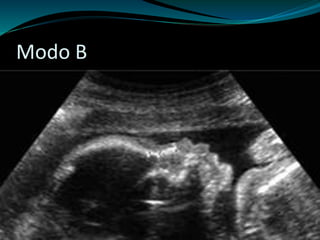

 Modo B

Modo B

Tipos de Ultra-Sonografia  Modo A  Modo M  Modo B  Modo D